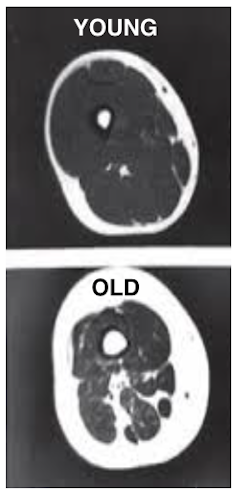

We have previously looked at several body systems that we know decline with age, such as muscle and bone. At mid-life, people start losing muscle mass and strength at a rate of 1% to 2% per year, making it harder to carry out their normal activities such as climbing stairs. Our bones also become thinner with age and this can eventually lead to diseases such as osteoporosis.

We showed that the cyclists did not lose muscle mass or strength as they age, and their bones only became slightly thinner. We then went on to examine a body system that was not so obviously influenced by physical activity – the immune system.